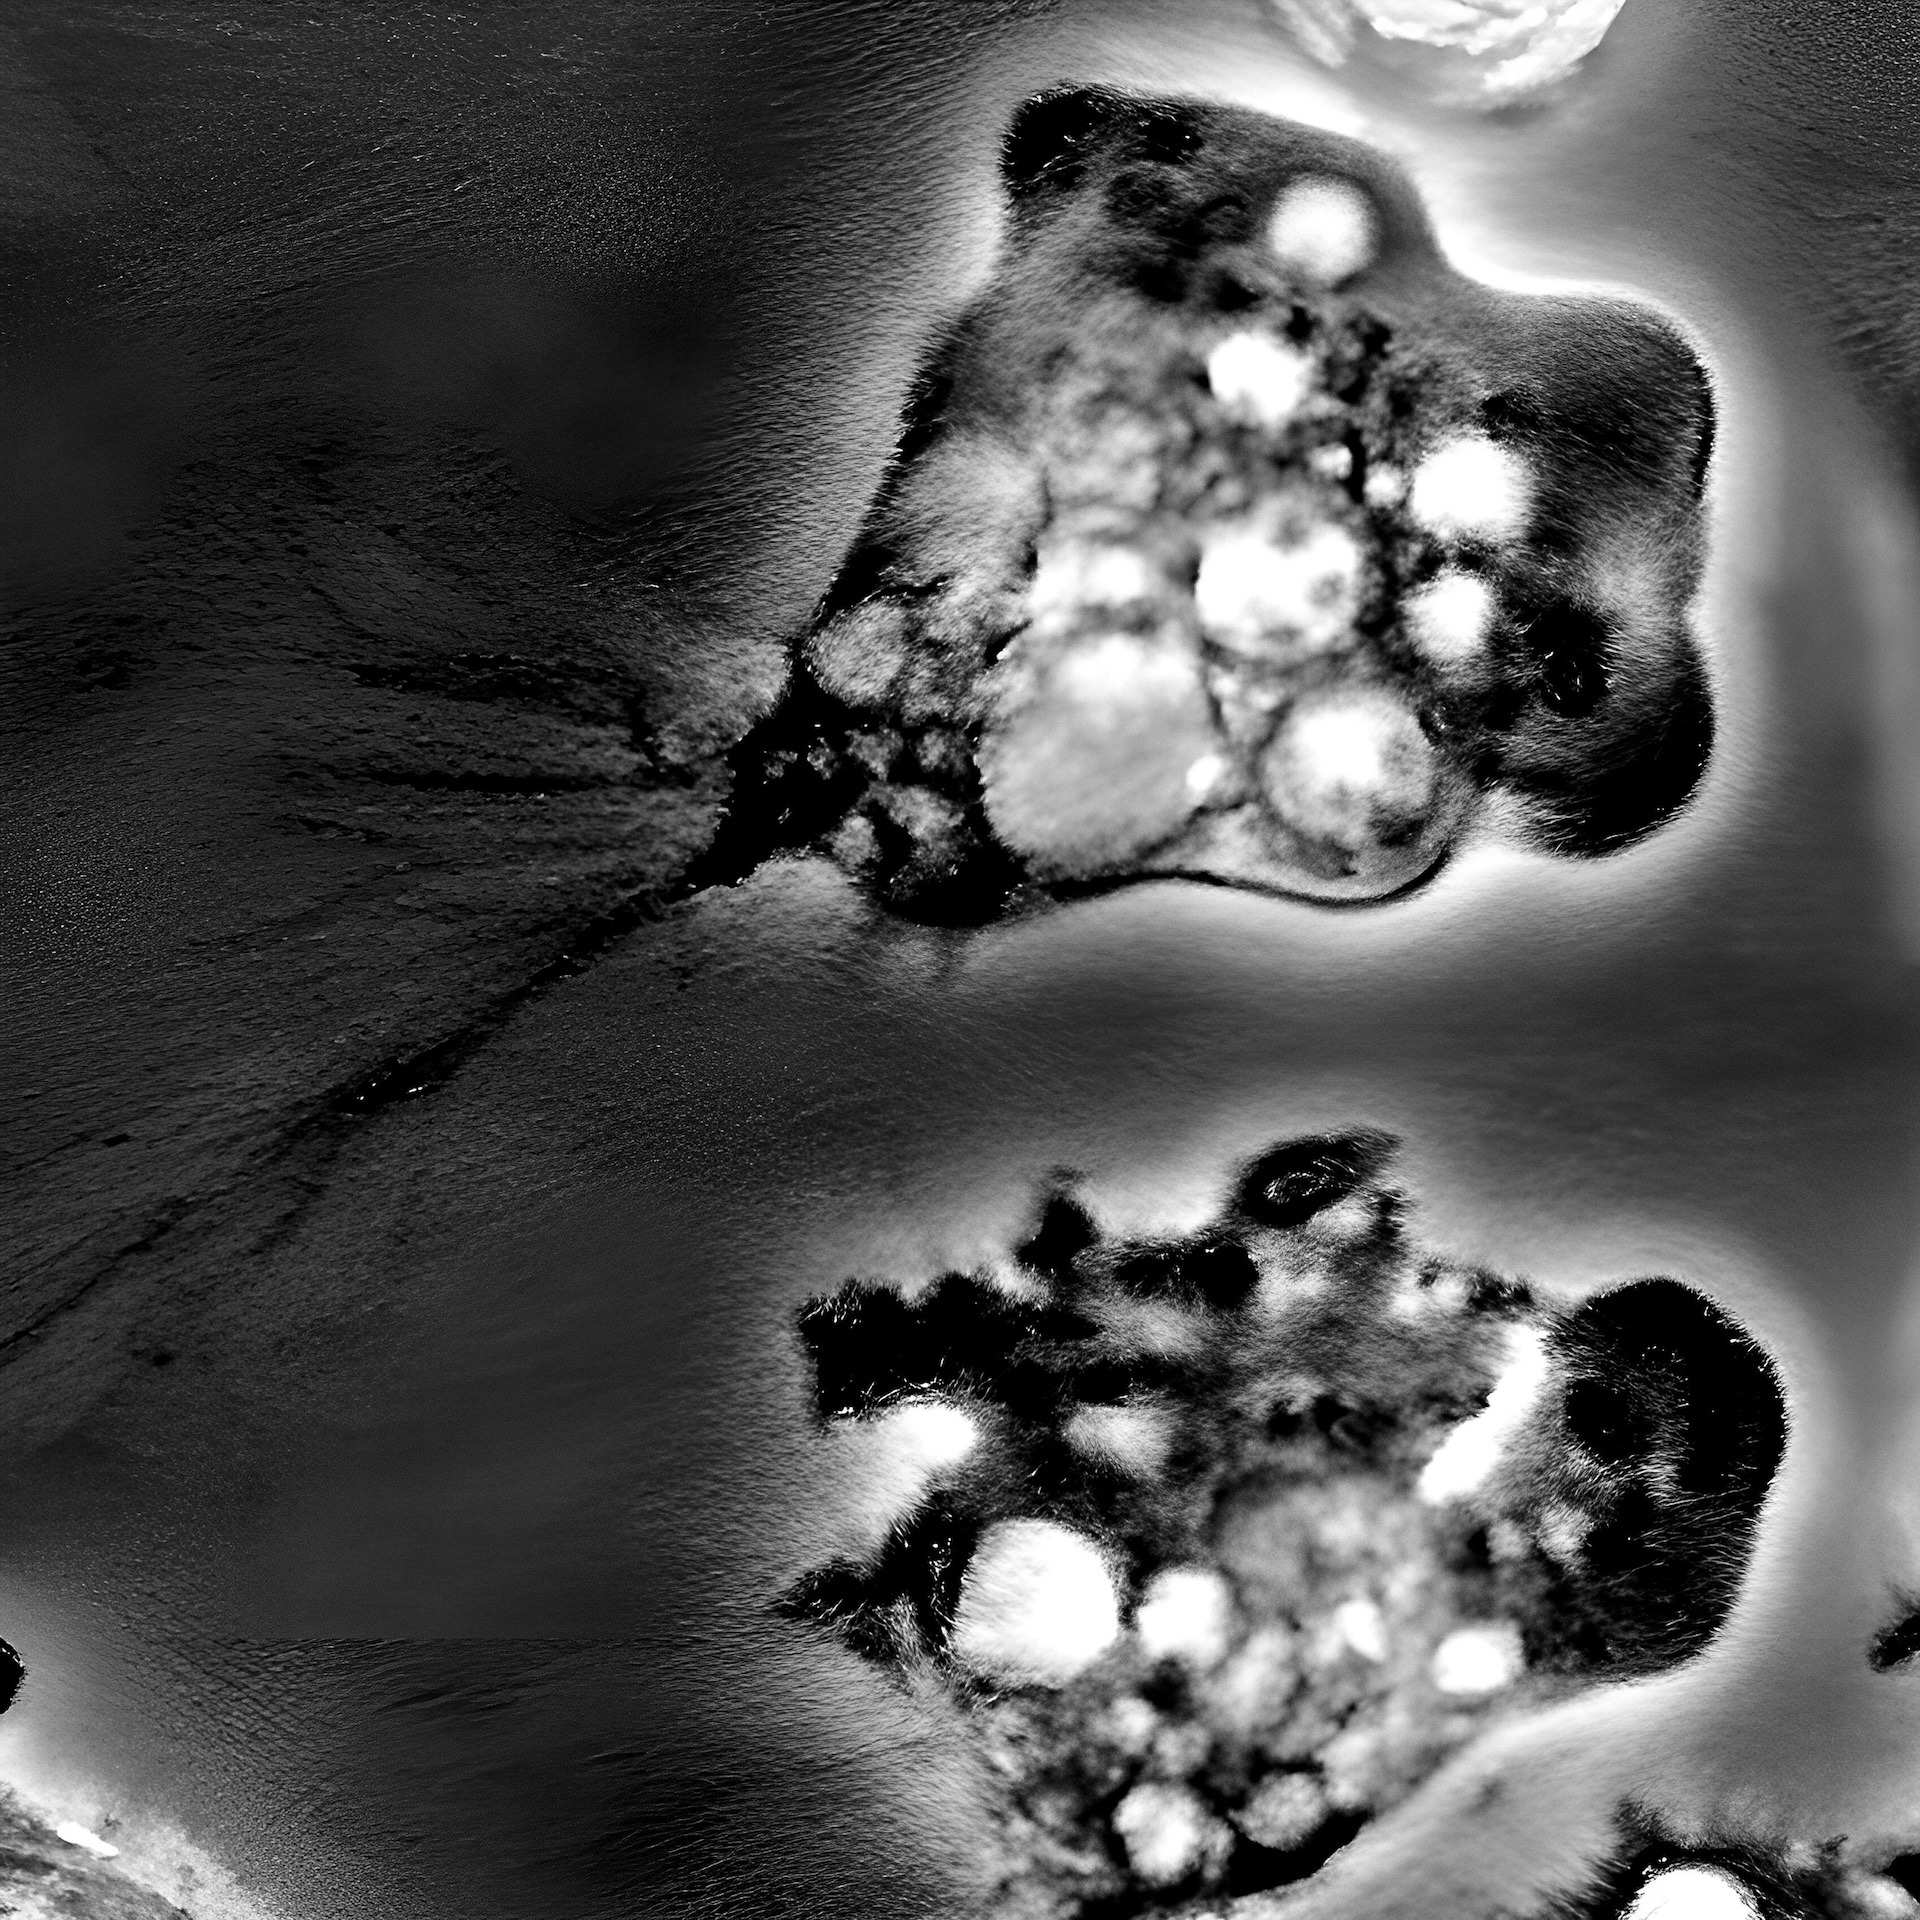

A image of N. fowleri under the microscope. (Image credit: BSIP SA via Alamy Stock Photo)

A microscopic image of amoebic meningoencephalitis caused by N. fowleri. (Image credit: Smith Collection/Gado via Getty Images)